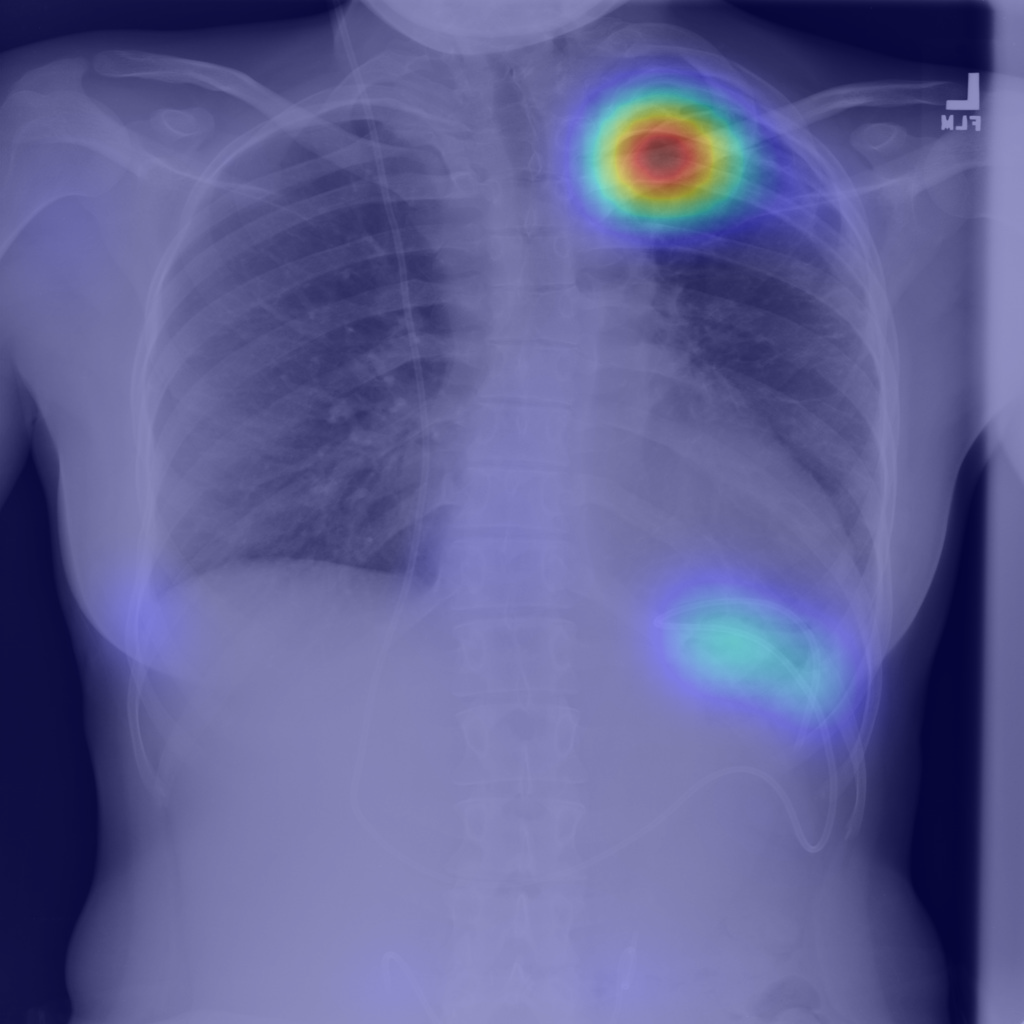

Refer to caption

(a) Image

(b) Step1.CAM

(c) Step2.IRNet

(d) Step3.Segm

(e) Mask

Figure 2: Segmentation predictions for (a) a random image from test set of SIIM-ACR Pneumothorax produced at each step of our approach: (b) CAM extraction, (c) IRNet, (d) U-Net segmentation, compared to (e) ground truth mask.